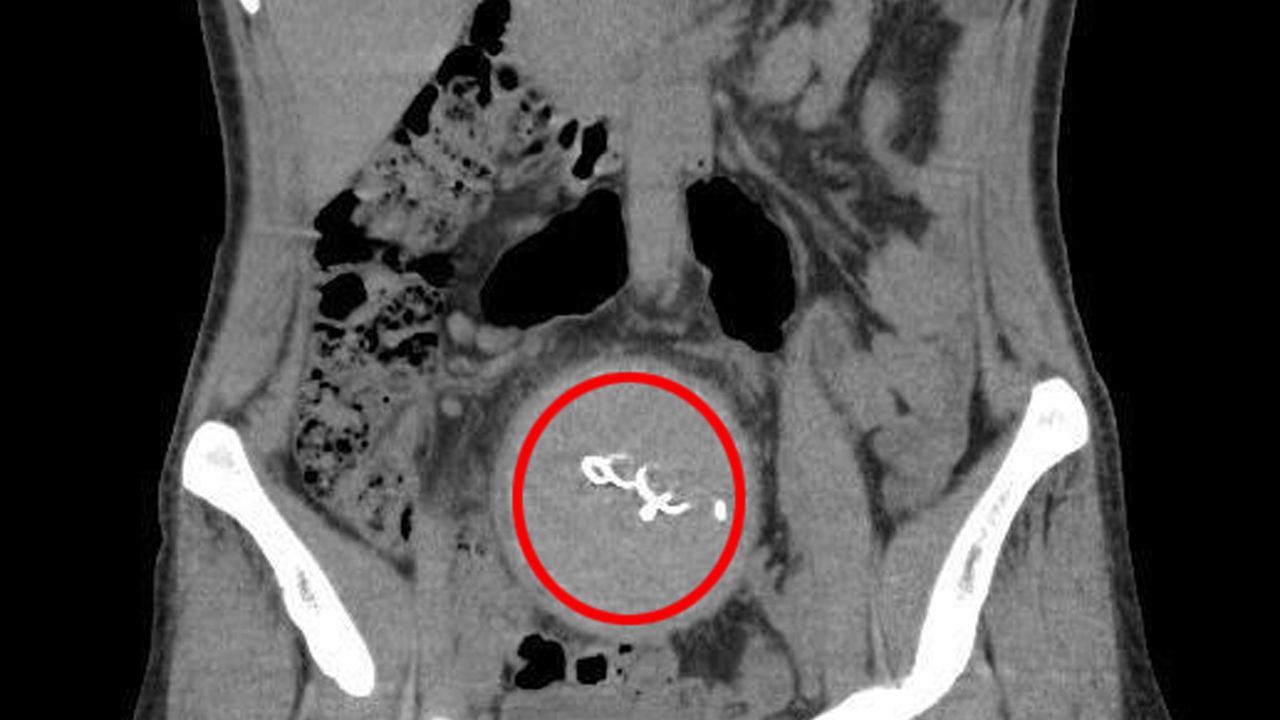

Burada yapılan kontrolde, doktor acil tomografi çektirmesini istedi. 2023 yılının Ağustos ayında çekilen tomografide, Y.S.'nin vücudunda doğum sonrası unutulan sargı bezi görüldü. Şoke olan Y.S., 2 yıldır yaşadığı ağrılara ihmalin sebep olduğunu öğrendi. Y.S.'nin karnında unutulan yaklaşık 30 santimetre uzunluğundaki gazlı bez ameliyatla alındı. Y.S., hastane ve süreç içerisinde ihmali bulunan doktorlar hakkında savcılığa suç duyurusunda bulundu.